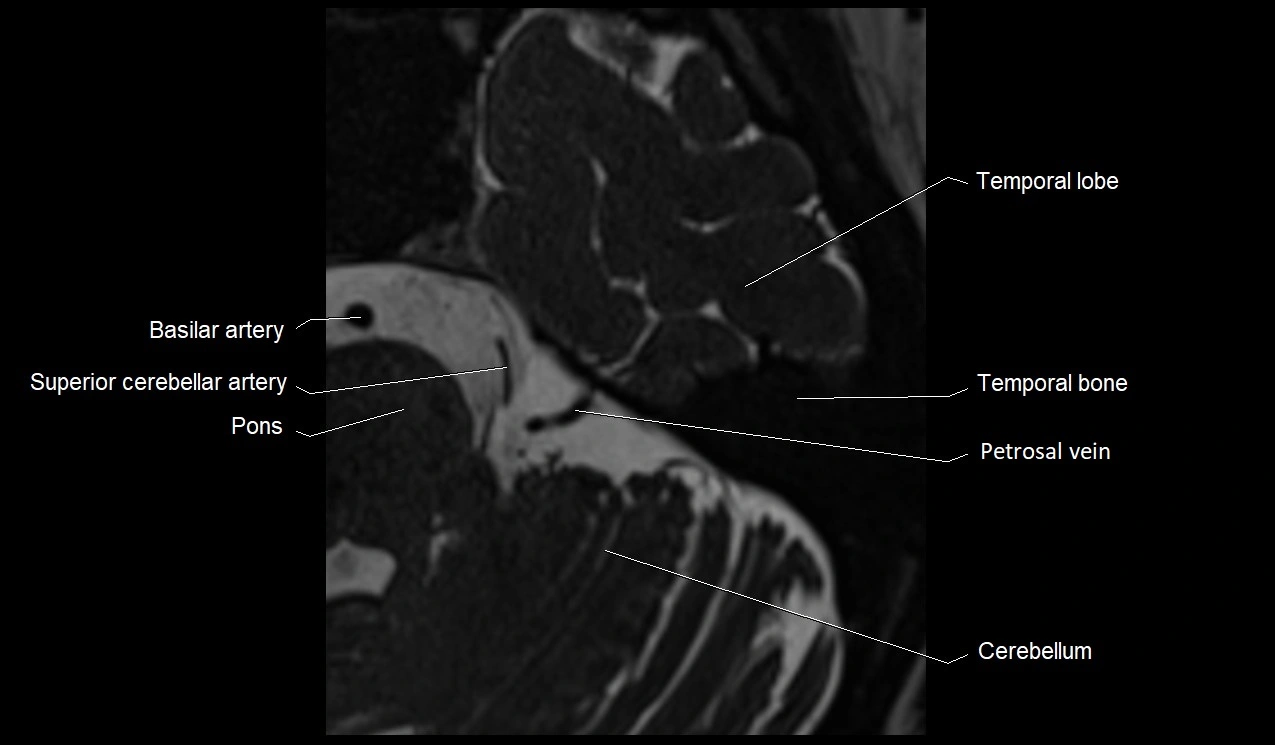

MRI images

image